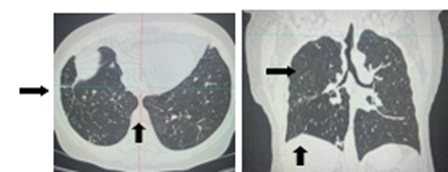

С января 2025 г. пациентка продолжает получать лечение в амбулаторных условиях. Терапию переносит хорошо. МСКТ ОГК от 10.02.2025: Состояние правого легкого после операции, в проекции корня легкого цепочка послеоперационных швов. По легочным полям с обеих сторон фиброз, очаги различных размеров, с отграниченными контурами. Просвет правого главного бронха значительно сужен. Средостение не смещено, не расширено. Свободной жидкости в плевральной полости нет (рис. 3).

Рис. 3. МСКТ ОГК от 10.02.25: По легочным полям с обеих сторон фиброз, очаги различных размеров, с отграниченными контурами. Просвет правого главного бронха значительно сужен. Источник: составлено авторами по результатам данного исследования

У пациентки имел место рецидив специфического процесса. В 2024 г. диагноз диссеминированного туберкулеза легких с поражением бронха был поставлен через несколько месяцев после появления первых признаков заболевания, причем решающим фактором в постановке диагноза явилась выполненная фибробронхоскопия с биопсией. Появление высокой температуры тела, слабость, респираторная симптоматика, изменения на МСКТ ОГП от 24.03.2024, отсутствие КУМ в мокроте изначально позволило выставить диагноз двусторонней пневмонии, а длительный кашель и одышка со свистом в груди, сухие рассеянные хрипы – расценить как проявления ХОБЛ. Однако отсутствие положительной клинико-рентгенологической динамики в процессе антибактериальной терапии, характер изменений на КТ при поступлении, а также указания на ранее перенесенный туберкулез легких заставляли сомневаться в диагнозе «пневмония» и заподозрить специфический процесс в легких. В описанном примере у пациентки с 2023 г. основными жалобами были приступообразный кашель со скудной мокротой, постоянная одышка при физической нагрузке со свистом в груди, по данным спирометрии от 2023 г. – средне-тяжелые нарушения функции вентиляции по обструктивному типу, в анамнезе указание на длительный стаж курения. Все эти данные позволили в амбулаторных условиях диагностировать ХОБЛ и начать проводить базисную терапию. В дальнейшем стало очевидным, что явления бронхиальной обструкции были обусловлены не сопутствующей ХОБЛ, а специфическим поражением бронхиального дерева, о чем свидетельствовали отсутствие какого-либо положительного эффекта от лечения ХОБЛ, преобладание сухих свистящих хрипов справа, данные ФБС и КТ ОГК от 02.2025 (просвет правого главного бронха значительно сужен).